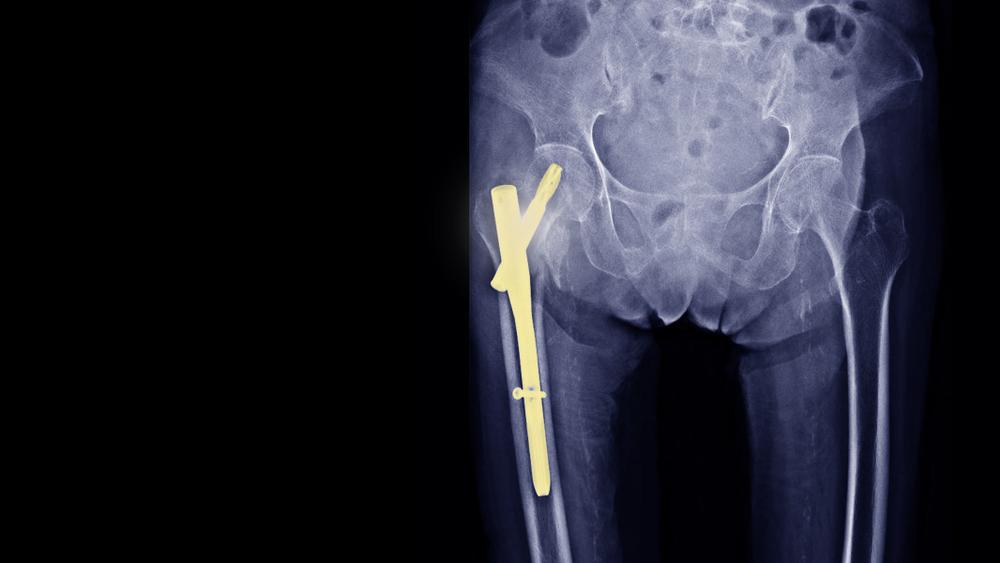

Pen adalah alat pendukung seperti pelat, sekrup, batang, dan kabel yang terbuat dari stainless steel atau titanium. Alat ini biasanya akan dokter gunakan pada operasi tulang, seperti:

• membantu tulang yang patah berada pada posisinya saat masa pemulihan,

• menyatukan tulang secara permanen (arthrodesis),

• mengubah bentuk tulang (osteotomy).

Nah, biasanya, setelah tulang sembuh total, dokter akan merekomendasikan pada Anda untuk menjalani operasi lepas pen. Namun, keputusan untuk menjalani operasi tersebut tetap berada pada tangan Anda sebagai pasien.